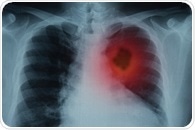

| | | Study shows protective cells reduce lung cancer risk in ex-smokers A new study could explain how lung cancer risk is reduced by quitting smoking. Published in the journal Nature in January 2020, the study shows that ex-smokers have a greater number of lung cells that have healthy genes compared to current smokers. Healthy genes are less likely to transform into cancerous cells. | |